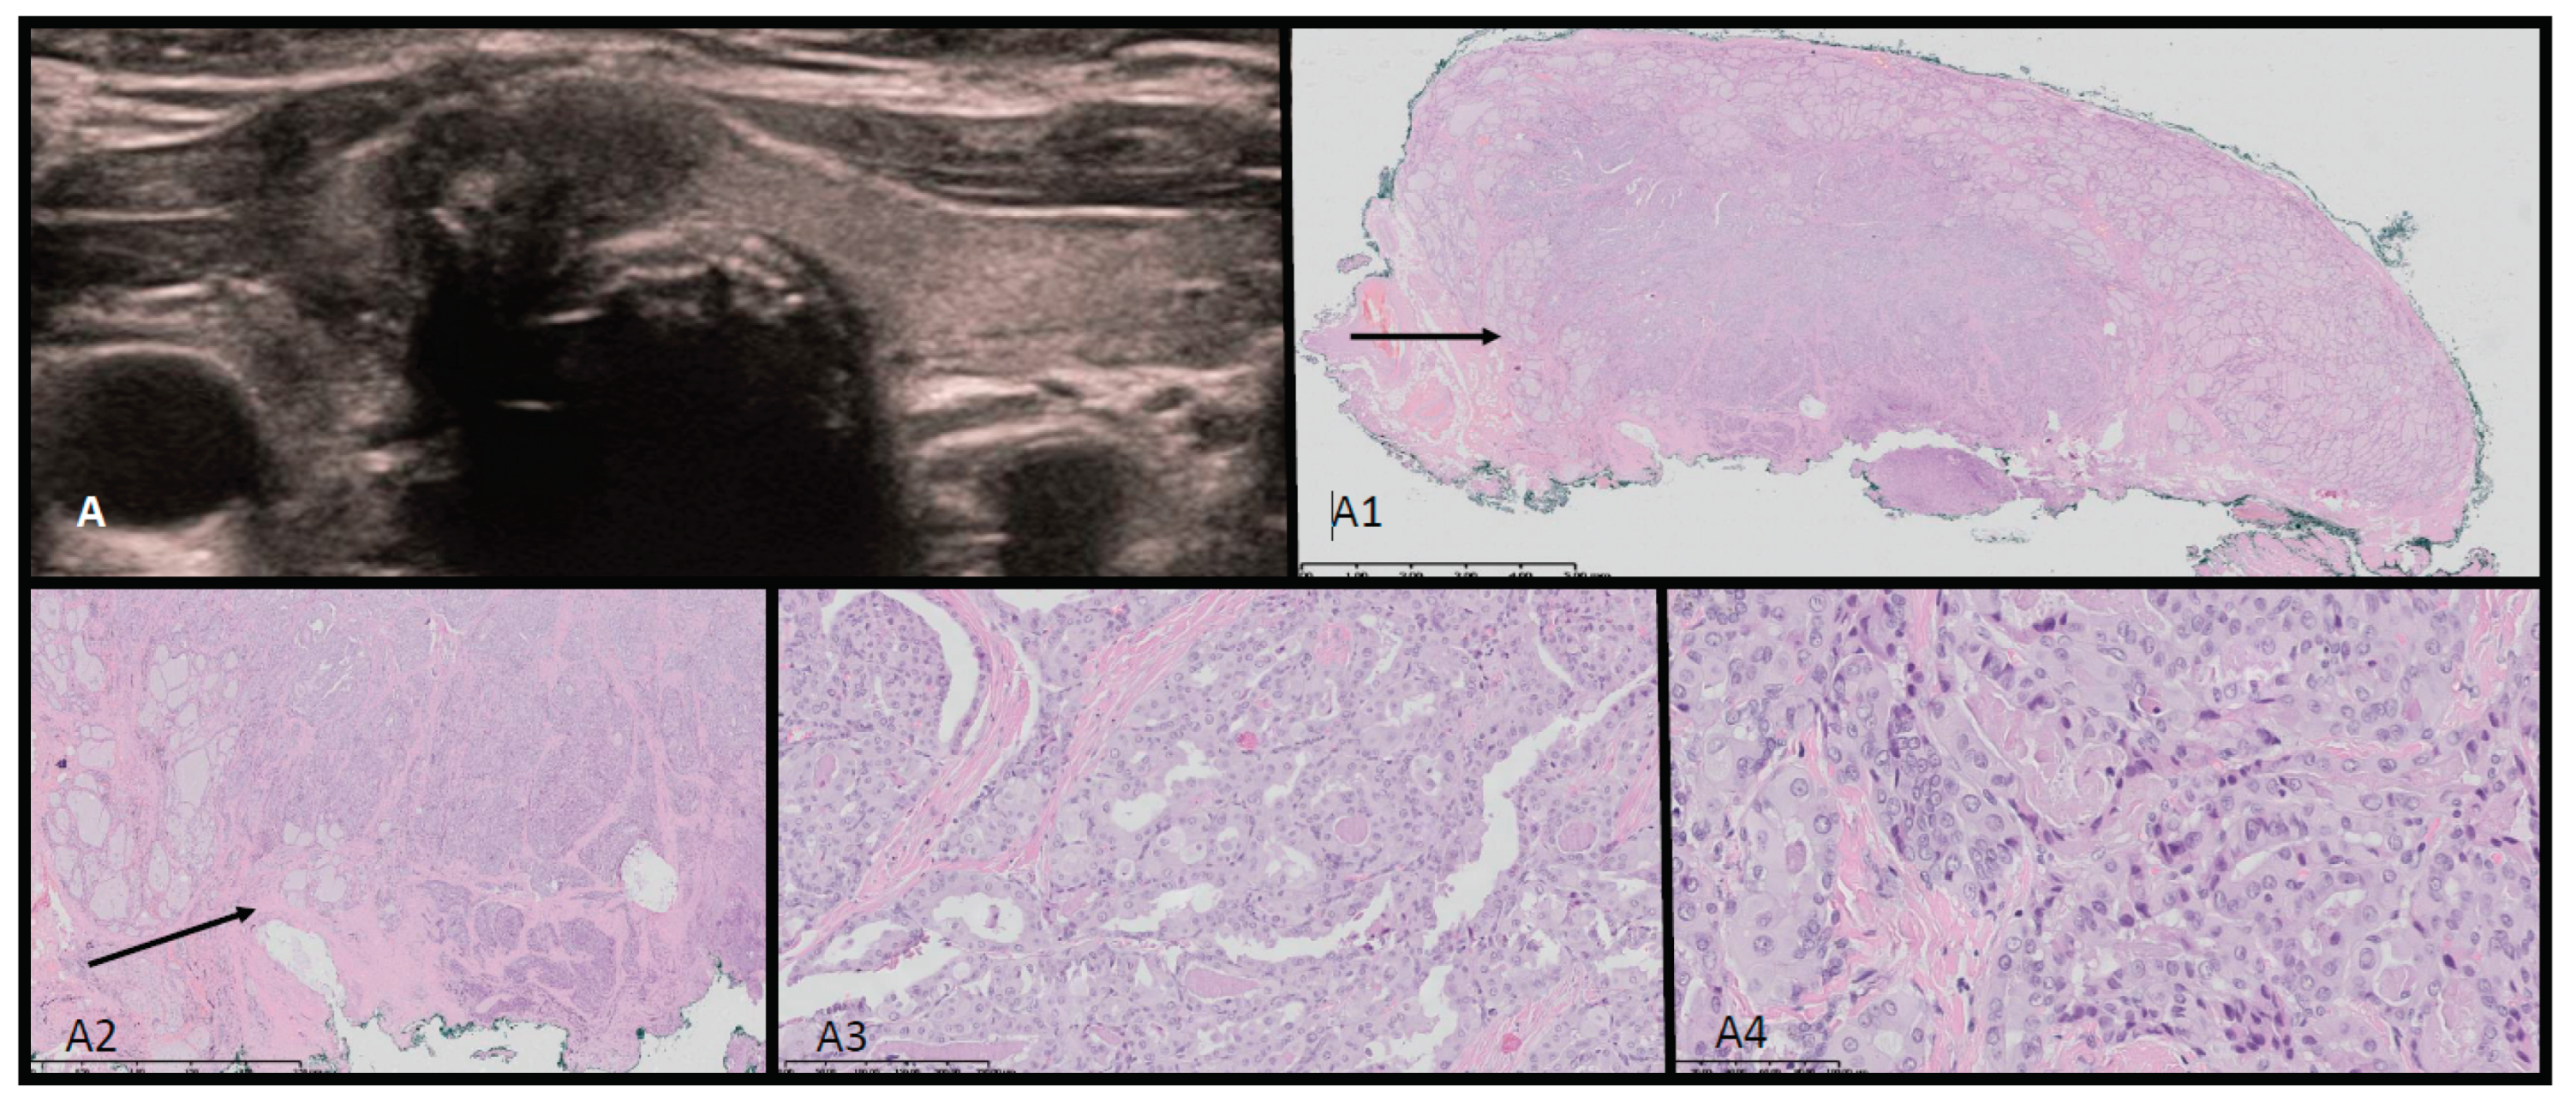

Point-of care ultrasonography was performed by the consulting endocrinologist. A thyroid ultrasound scan identified a multinodular 68 ml goiter with 15 isoechogenic cystic-solid lesions containing macrocalcifications. Vascularization was not increased in the solid parts of the nodules. An abdominal ultrasound identified a 5.7 x 6.9 cm solid mass in the right adnexal region, displacing the uterus to the left. Magnetic Resonance Imaging findings were consistent with either arrhenoblastoma or dysgerminoma. A right ovariectomy was performed, and histopathology confirmed a moderately differentiated Sertoli-Leydig cell tumor. Ultrasound-histopathological analysis is presented in Figure 2(A-A4).

Figure 2. Ultrasound-histopathological assessment of SLCT moderately differentiated in Patient 1. A- 5.7x6.9 cm solid mass in the right adnexal region seen on US scan. A1-A4: HE histopathological assessment. The SLCT is composed of cords, solid and microcystic areas of small Sertoli cells [red arrows], as well as scattered and clustered Leydig cells with abundant eosinophilic bright-pink cytoplasm and round nucleus [yellow arrows]. Fibrous stroma [black arrows] with lymphocytic infiltration is visible. The low magnification (A1) shows hypo- and hypercellular nodules predominantly built by Sertoli cells presenting different architecture. The tumor was confirmed with immunohistochemistry [CK AE1/AE3 positive in Sertoli cells, vimentin [+], and calretinin, CD99, WT1 – positive in the part of cells, and also EMA and CD34 – negative [data not shown]. The proliferation index of Ki67 is approx. 40% and the mitotic figure count 11/ 10 HPF [high power field]. The tumor was totally resected with minimal margin of 2.7 mm. In the periphery the ovarian cortex with primary and vesicular follicles can be seen [green arrows].